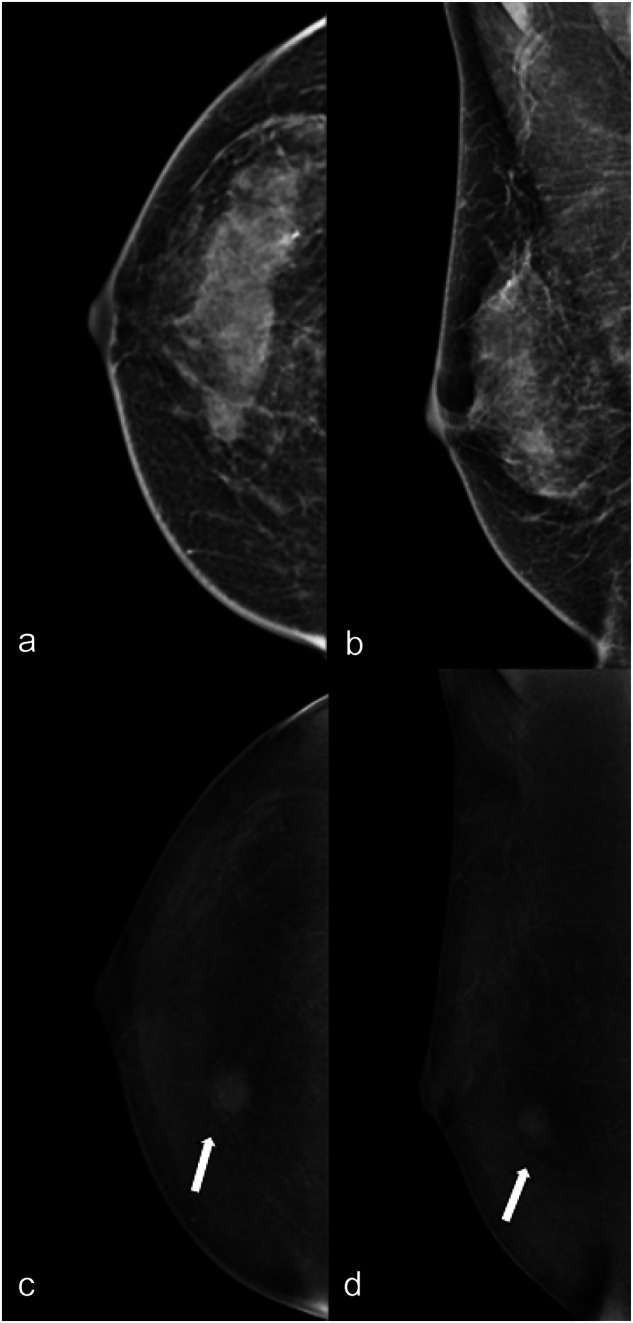

Fig. 3.

LE (a, b) and RC (c, d) CEM images of the right breast of a 69-year-old patient. The three readers evaluated in separate sessions ACR density (b, unanimously); type of lesion (no lesion for two of the three readers, mixed for the third); presence/absence of associated architectural distortion (absence, unanimously) on LE images; type of enhancement (enhancing asymmetry for two of the three readers, evidenced by white arrows on CC view; non-mass for the third, evidenced by white arrowhead on MLO view); and lesion conspicuity (moderate for two of the three readers, low for the third) and mass enhancement descriptors (enhancing asymmetry internal pattern of enhancement homogeneous for two of the three readers, non-mass distribution focal and non-mass internal pattern of enhancement homogeneous for the third) on RC images. The level of suspicion was BI-RADS 1 for two of the three readers and for the third on LE and on RC BI-RADS 4, unanimously. Histology after US-guided biopsy was atypical ductal hyperplasia, final diagnosis at surgery was ductal carcinoma in situ

The inter-agreement was substantial for the type of enhancement on RC images (no enhancement, mass, non-mass, enhancing asymmetry) (ĸ = 0.664, Table 2). There was a moderate agreement for lesion conspicuity (ĸ = 0.517). The overall agreement for mass enhancement descriptors was moderate for shape (ĸ = 0.523) and margins (ĸ = 0.566) and substantial for an internal pattern of enhancement (ĸ = 0.618) (Fig. 2). The agreement for non-mass enhancement descriptors was fair for distribution (ĸ = 0.387) and moderate for an internal pattern of enhancement (ĸ = 0.415). The agreement for enhancing asymmetry descriptors was fair (ĸ = 0.247) (Fig. 3).